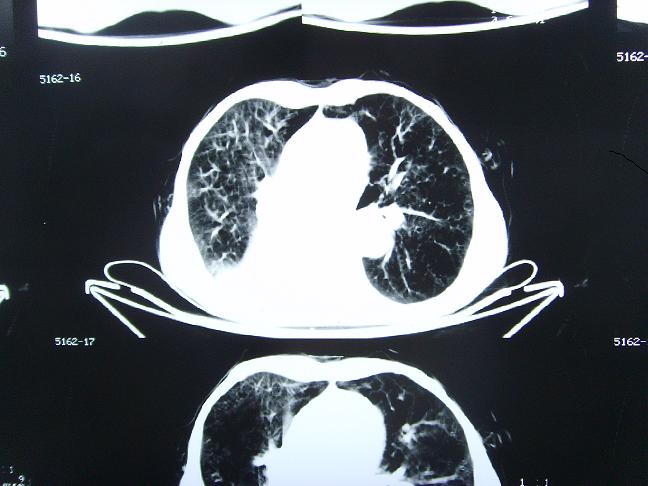

考虑  右肺新生物伴右下肺阻塞性肺炎,肺不张.右侧胸腔积液

考虑:右侧中心型肺癌伴下肺肺不张。

1)右肺中央型肺癌伴右肺下叶肺不张。2)慢性支气管炎,肺气肿。3)右侧胸腔积液。

右肺中央型肺癌伴右肺下叶肺不张。慢支肺气肿。右侧胸腔积液。